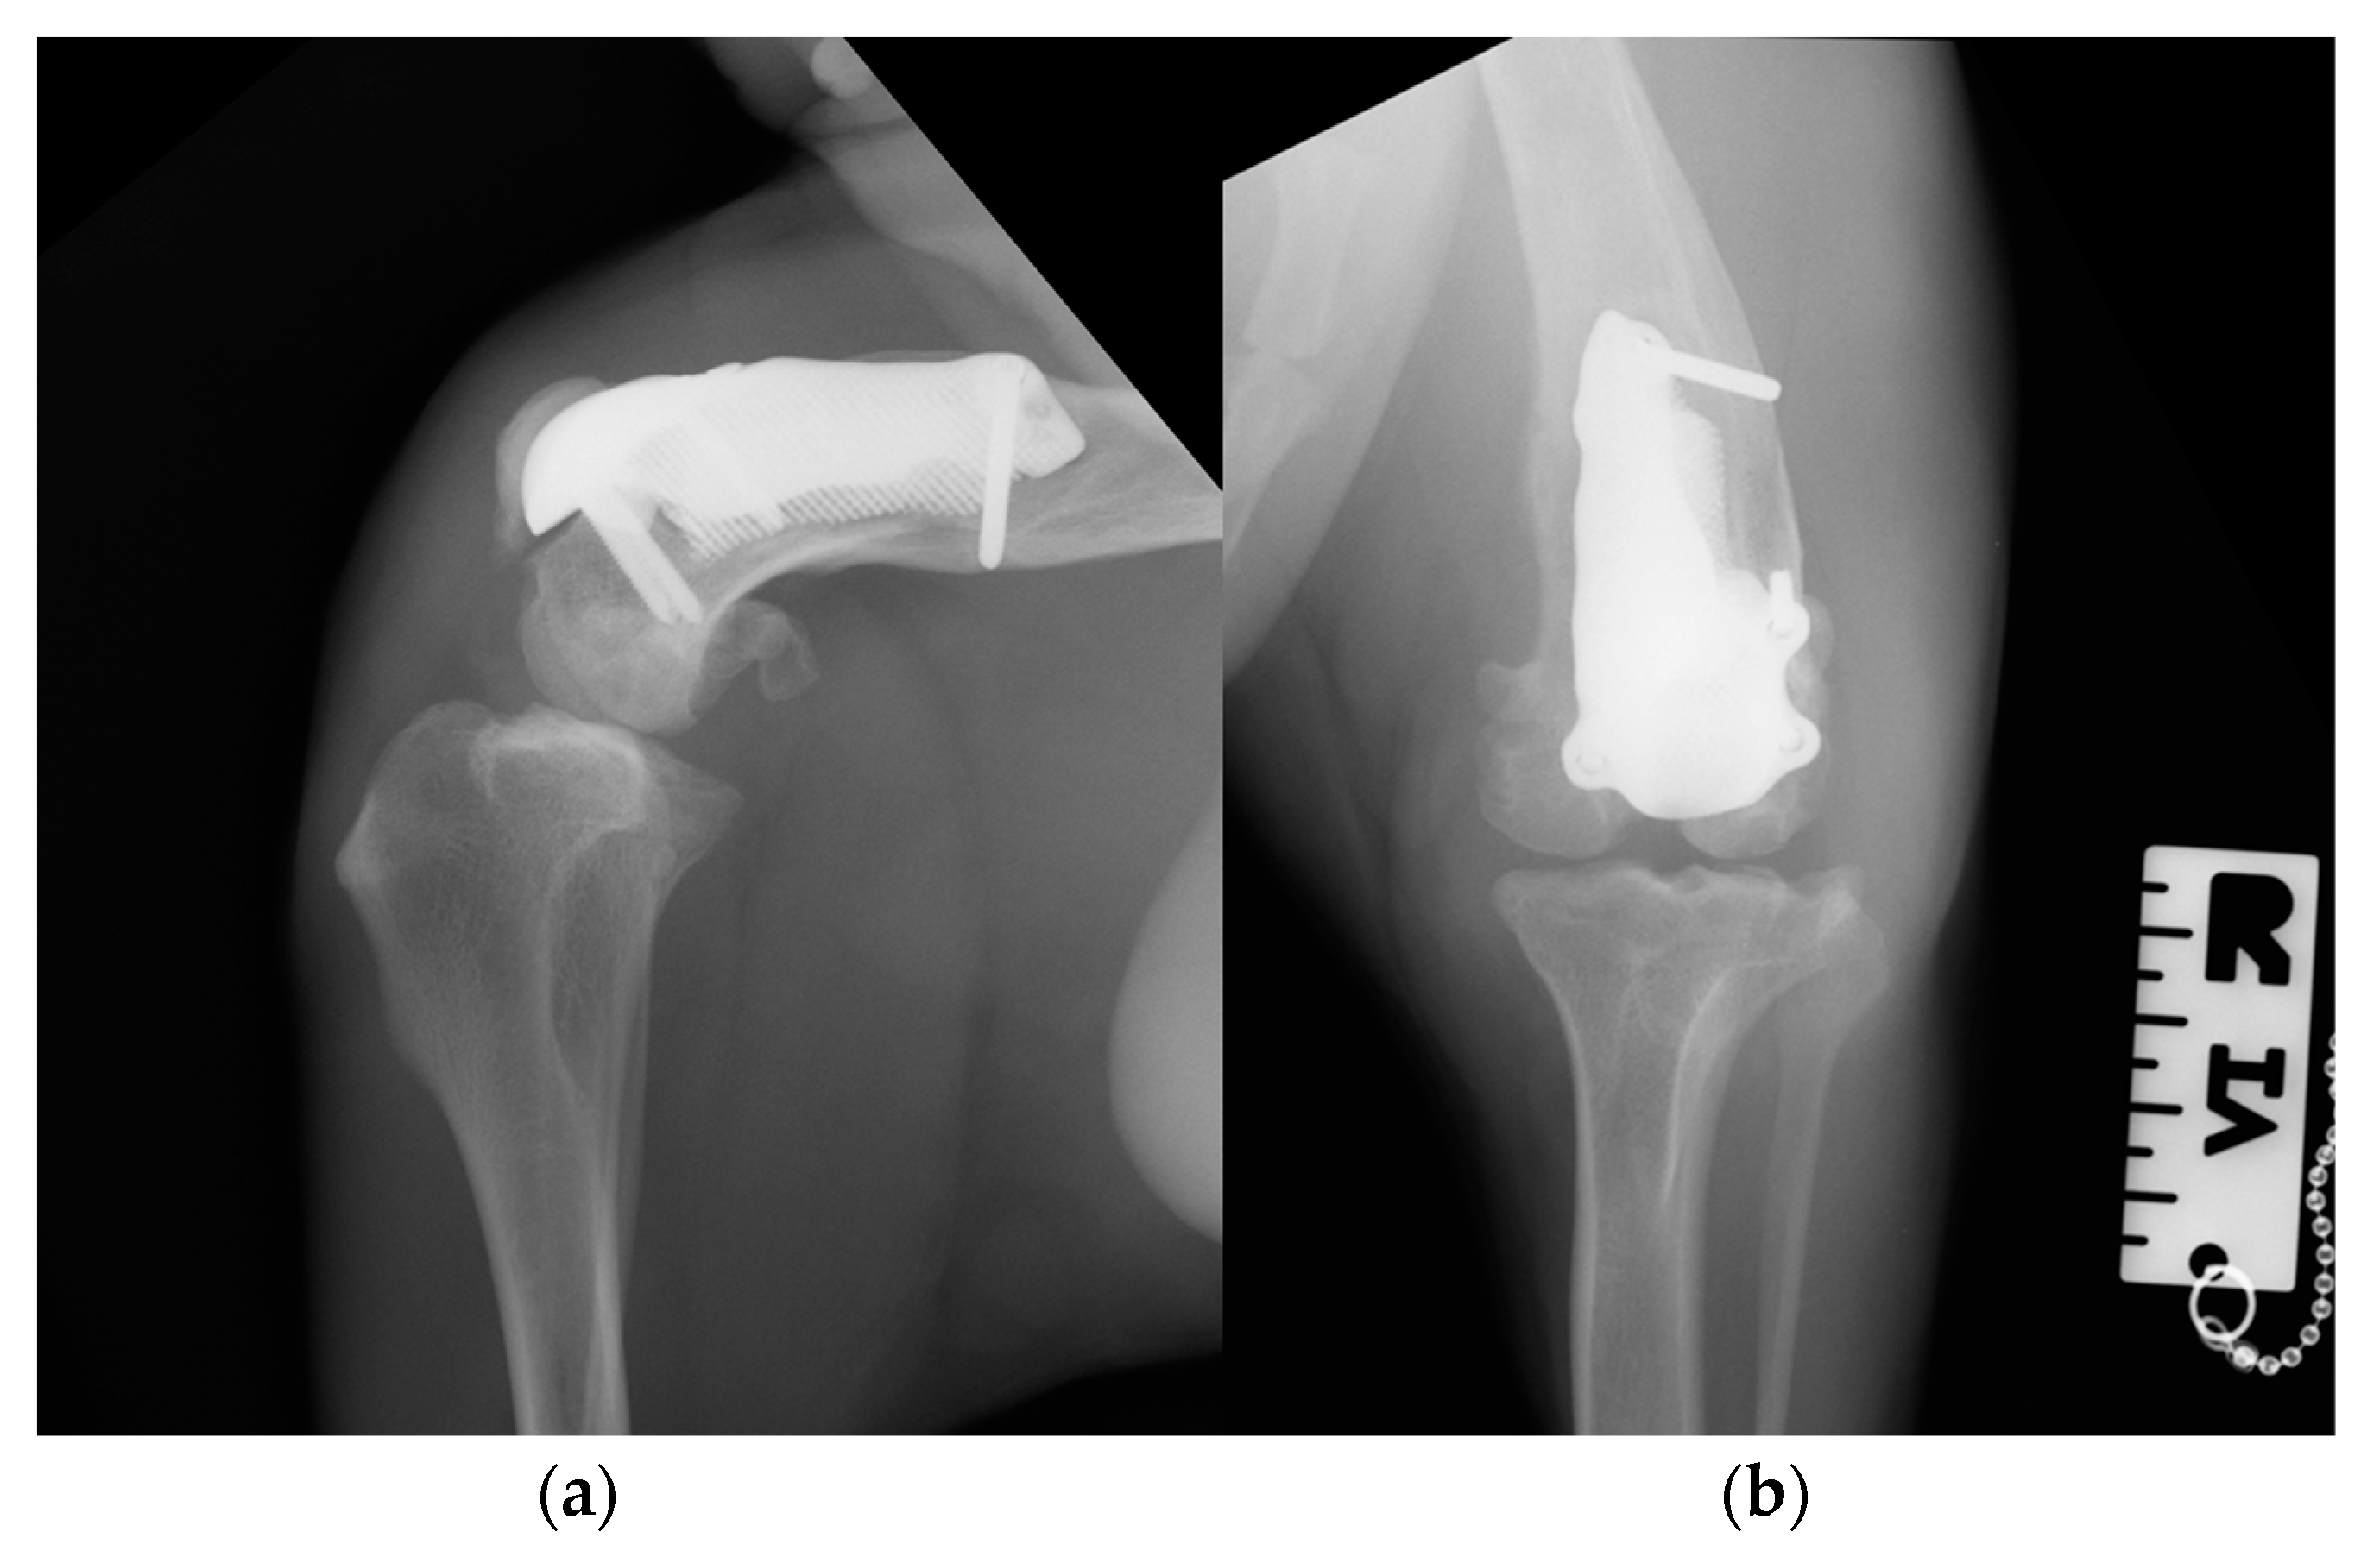

Figure 12. Twelve-month postoperative medio-lateral (a) and caudo-cranial (b) radiographs of stifle joint showing a good osteointegration of the implant and osteoarthritic changes in the distal pole of the patella compared to postoperative and 3-month postoperative radiographs.

At the 6-, 12- and 18-month follow-up (Video S3c), the orthopedic evaluation revealed crepitus, but a grade 0 right limb lameness and absence of patellar ligament desmitis and palpation of the right stifle joint did not elicit pain. The estimated angle of extension and flexion of the right stifle was 160–80°, respectively, while the ROM of the contralateral healthy limb was 160° in extension and 40° in flexion. The thigh circumference of the pathologic limb was 40 cm compared with 47 cm of the healthy one. The radiographic images showed a good osseointegration of the implant and progression of degenerative changes in the distal pole of the patella (Figure 12).